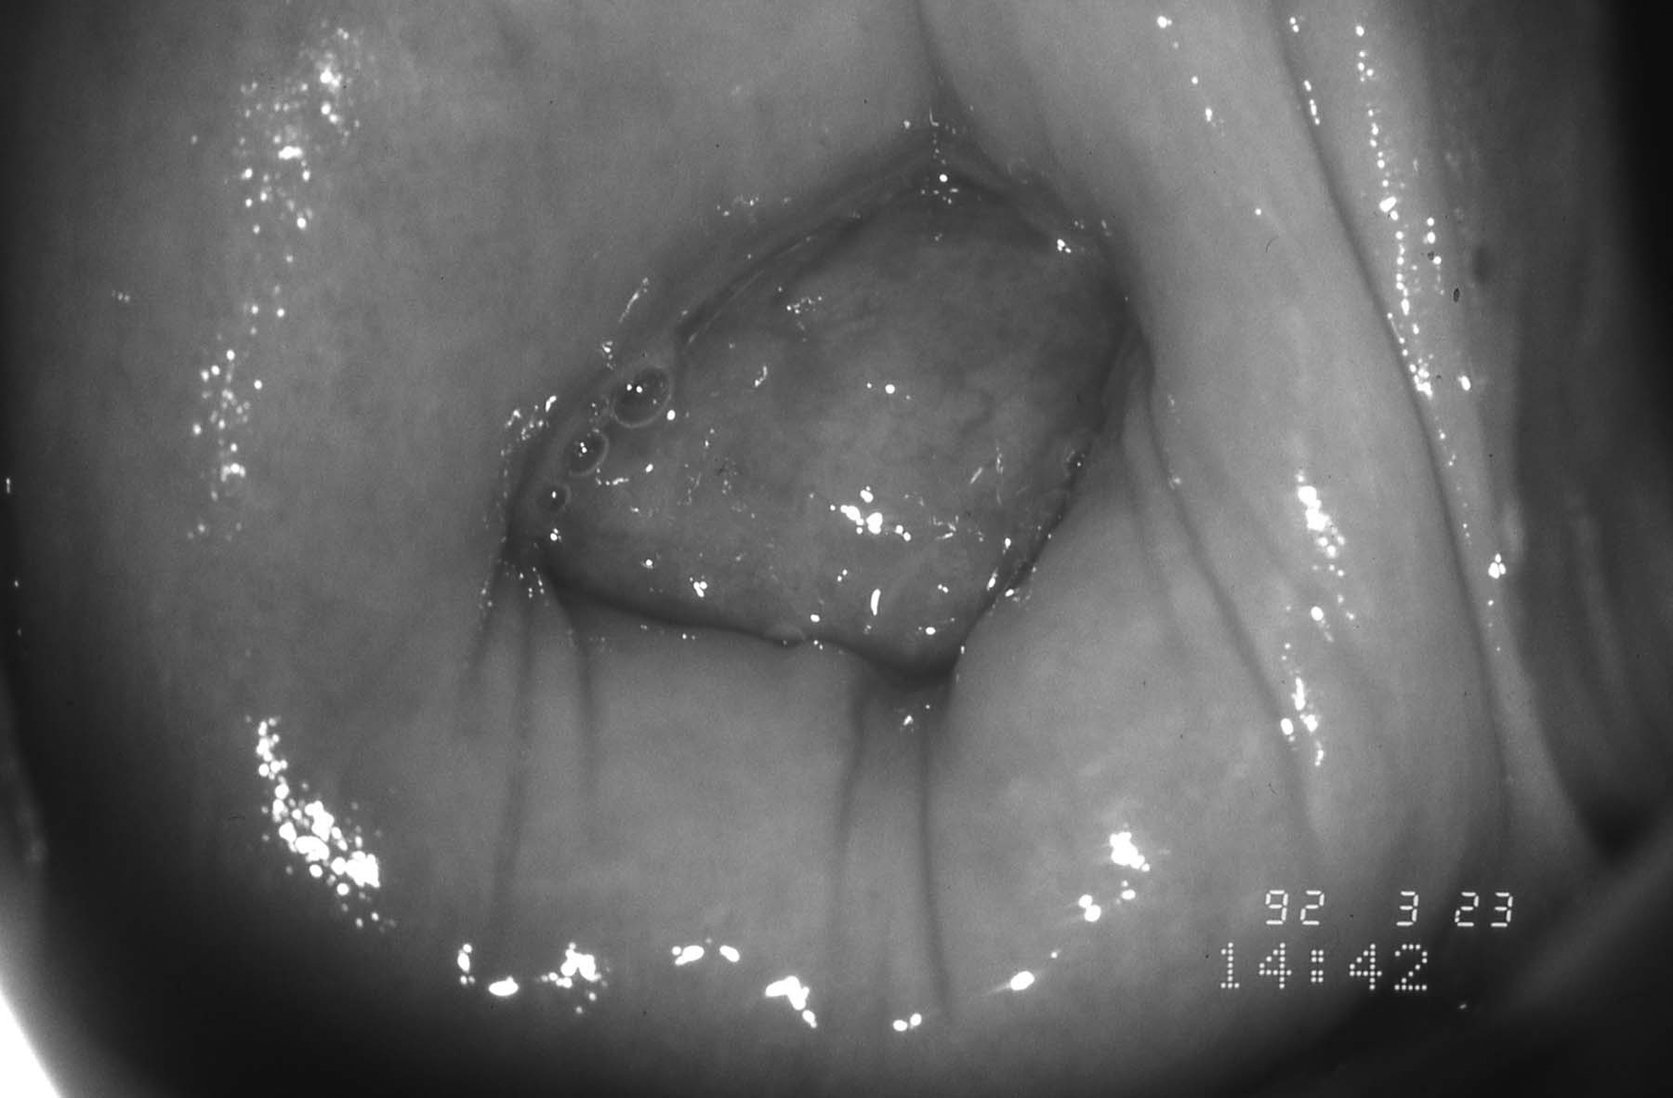

5 . 3  -  Fibromes ou polypes fibreux accouchés par le col

Il s’agit d’une tumeur bénigne accouchée par le col, généralement plus volumineuse que les polypes muqueux.

Figure 18.12 Fibrome partiellement accouché par le col

Figure 18.12 Fibrome partiellement accouché par le col.

Ils naissent dans la cavité utérine et nécessitent un contrôle histologique à la recherche d’un sarcome.